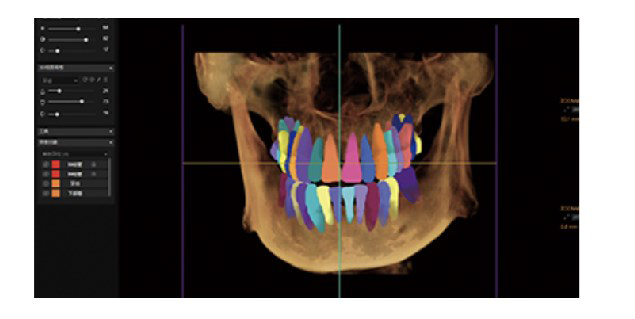

Segmentación dental automática.

Planificación del plan de ortodoncia.